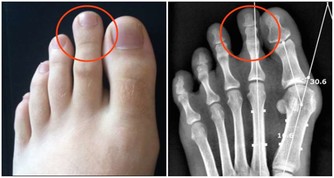

便秘造成的憩室,是大腸藏汙納垢的溫床 有些人在用力排便時,腸子因為壓力的關係,讓結腸壁較脆弱的地方像吹氣球一樣長出一個氣囊出來,就形成了憩室。它是一種良性的囊袋,是大腸最容易藏汙納垢的地方,如果不處理,久而久之就有形成大腸癌的可能。

憩室一旦長出來就不易消除,老人家和便秘者有百分之三十到四十的人都會有憩室,平時不痛不癢,就像盲腸一樣,如果沒有髒東西跑進去就沒事,但如果排泄物囤積其中,就容易發生感染或發炎。因此,已經有憩室的人應以斷食、灌腸來定期清除裡面的髒東西。